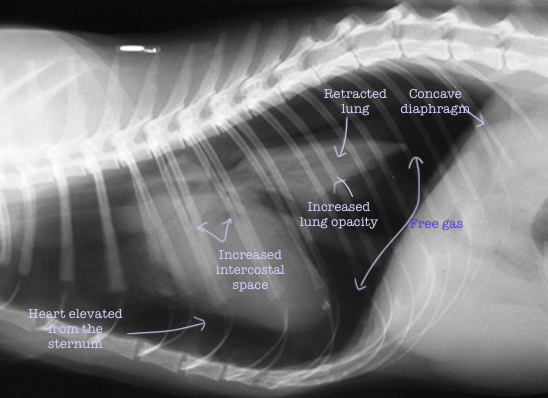

What are the three characteristic signs of a pneumothorax on a radiograph?

Heart elevated from the sternum Retraction of the lung lobes with free gas between the lung and the thoracic wall

Increased lung opacity

What are the five characteristic signs of a tension pneumothorax on a radiograph?

Heart always elevated from the sternum

Retraction of the lung lobes with free gas between the lung and the thoracic wall

Flat or concave diaphragm

Increased size of intercostal spaces